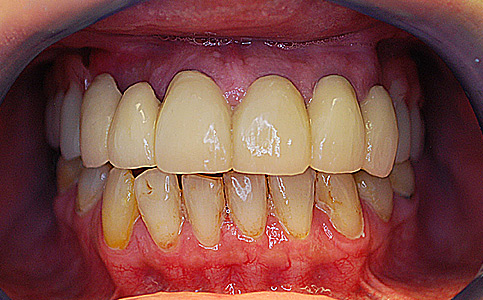

Przykład pełnej rehabilitacji protetycznej obejmujący leczenie biologiczne, uzupełnienie braków zębowych implantami oraz korony pełnoceramiczne w łuku górnym i dolnym. Spektakularna metamorfoza uśmiechu wykonana przez zespół Centrum Stomatologii i Ortodoncji FRESHmed odmieniła życie Pacjenta dodała pewności siebie i sprawiła, że z chęcią się uśmiecha.

Zobacz efekty przeciągając suwak w prawo lub w lewo.